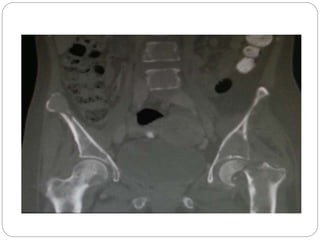

This document discusses 8 oncology cases. Case 1 involves a 40-year old female with right knee pain. Case 2 is a 28-year old male with a left subtrochantric fracture from a MVA who is now experiencing increasing left knee pain and swelling. Biopsy results showed high-grade osteosarcoma. Case 3 is a 30-year old female with breast cancer and bone metastases causing bilateral hip pain.